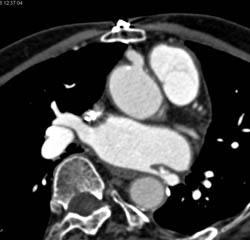

Plaque in LAD